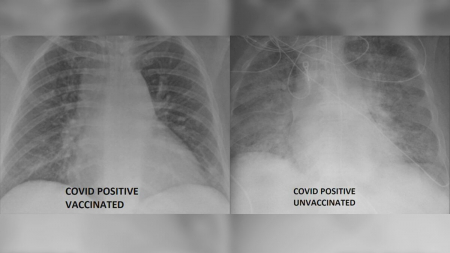

WinNews : เทียบเอกซ์เรย์ผู้ป่วยโควิด “ไม่ฉีดวัคซีน” กับผู้ป่วยที่ “ฉีดแล้ว”

ข้อมูลทางการแพทย์ ปรียบเทียบระหว่างปอดของผู้ติดเชื้อโควิด-19 ที่ได้รับการฉีดวัคซีนแล้ว กับผู้ที่ยังไ...